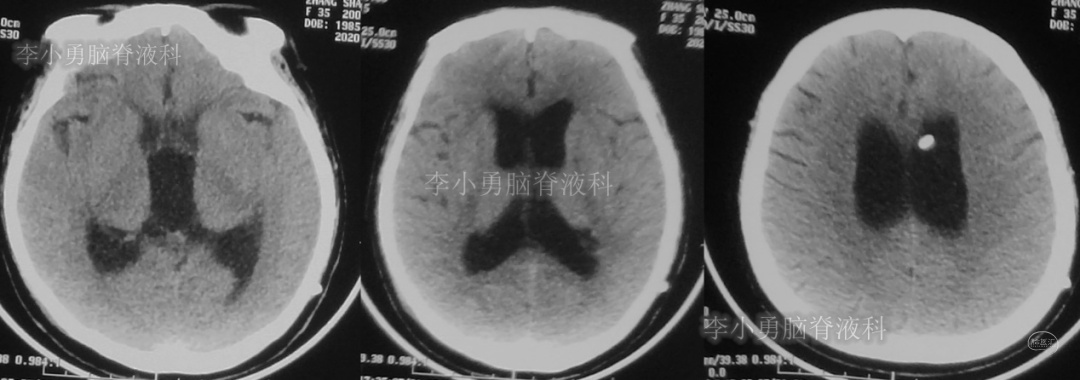

此次分流泵调压后1个月,即2018年12月11日,患者第3次出现头痛,而且头痛逐渐加重并昏迷,急到当地的第1家医院行头颅CT(图-7)见脑室从缩小又变成扩大状态。

图-7:2018年12月11日头颅CT

第3次调压后18天,即2018年12月29日,患者恢复好,在当地第1家医院复查头CT(图-8)见脑室明显缩小。

图-8:2018年12月29日头颅CT